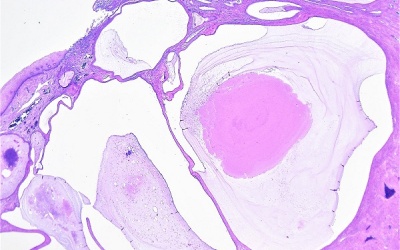

Nang naboth là u nang nhỏ hình thành trên bề mặt cổ tử cung - nơi kết nối giữa âm đạo và tử cung. Nang naboth cổ tử cung chứa đầy chất nhầy được tiết ra bởi các tuyến cổ tử cung.